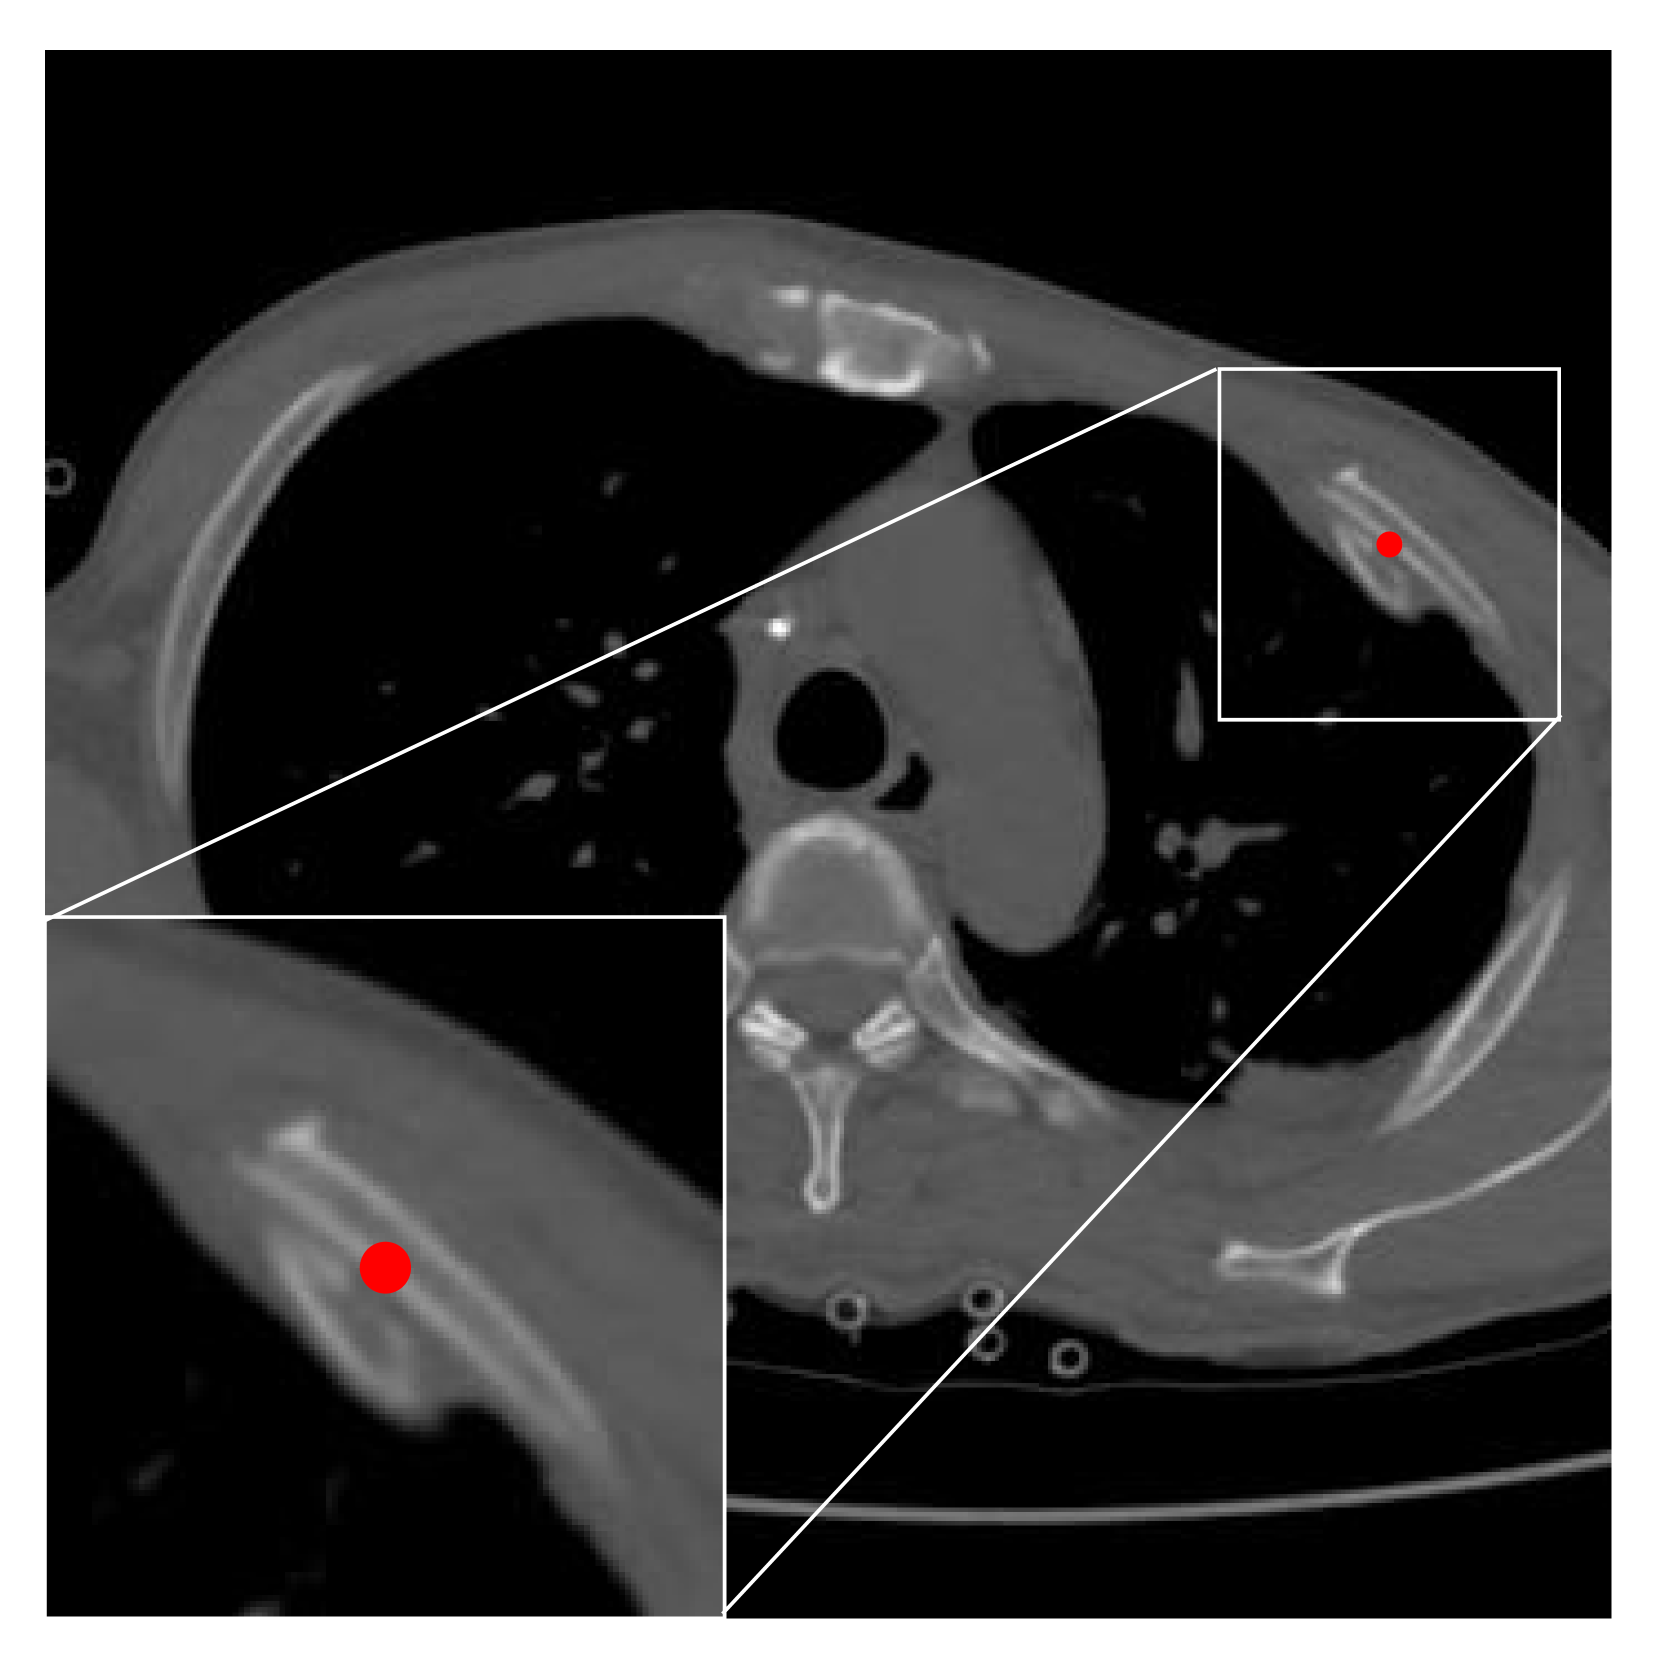

We further visualized a qualitative comparison in Fig. 4. It can also be observed that our proposed ORF-Netv2 detected the rib fractures from the CT images more correctly than other compared methods.

Refer to caption

Figure 4: Qualitative comparisons of the FCOS [23], UT [8], ORF-Net [14], and our proposed method on RibFrac and XRF. Ground truth, true positives, and false positives are annotated in red boxes, green boxes, and blue boxes, respectively.

We also compared ORF-Netv2 with other methods qualitatively with visualization shown in Fig. 4, where our proposed model accurately detected multiple fractures on the chest X-ray images.